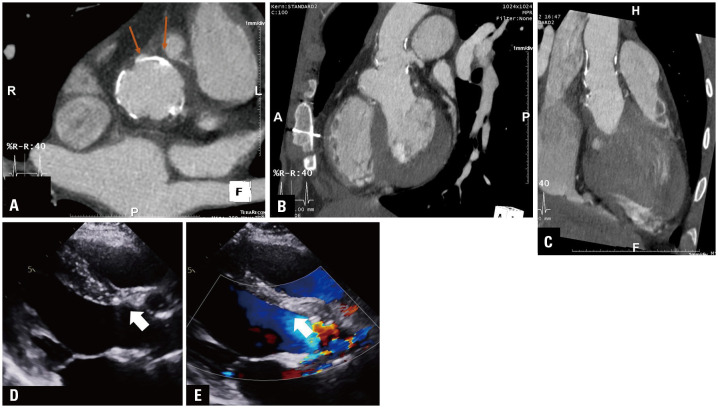

Aortic regurgitation (AR) in children is usually caused by congenital valve anomalies, and Behçet syndrome (BS) can be suspected in cases of isolated AR. Patients with BS undergoing aortic valve surgery due to aortic valve invasion have a high risk of complications, such as leakage around the valve and dehiscence. Cardiovascular involvement occurs in 7%-46% of adult patients with BS and is the main cause of mortality; however, its prevalence is unclear and rare in children. A 12-year-old boy was diagnosed with severe AR associated with BS. A progressive subaortic pseudoaneurysm was observed after aortic valve replacement. The periaortic intracardiac pouch was at risk of rupture; therefore, the patient underwent a Bentall operation. After the Bentall procedure, a newly developed subaortic pseudoaneurysm was detected below the prosthetic valve. However, the risk of rupture reduced as the subaortic pseudoaneurysm regressed with anti-inflammatory drugs alone without reoperation. Repeated surgery is inevitable in patients with BS undergoing aortic valve surgery due to the progressive chronic inflammatory reactions that present with a pseudoaneurysm. Here, we report an 8-year follow-up of a pediatric case of BS with subaortic pseudoaneurysm, highlighting the importance of close follow-up, medical management, and early diagnosis in treating this condition.

Abstract Image